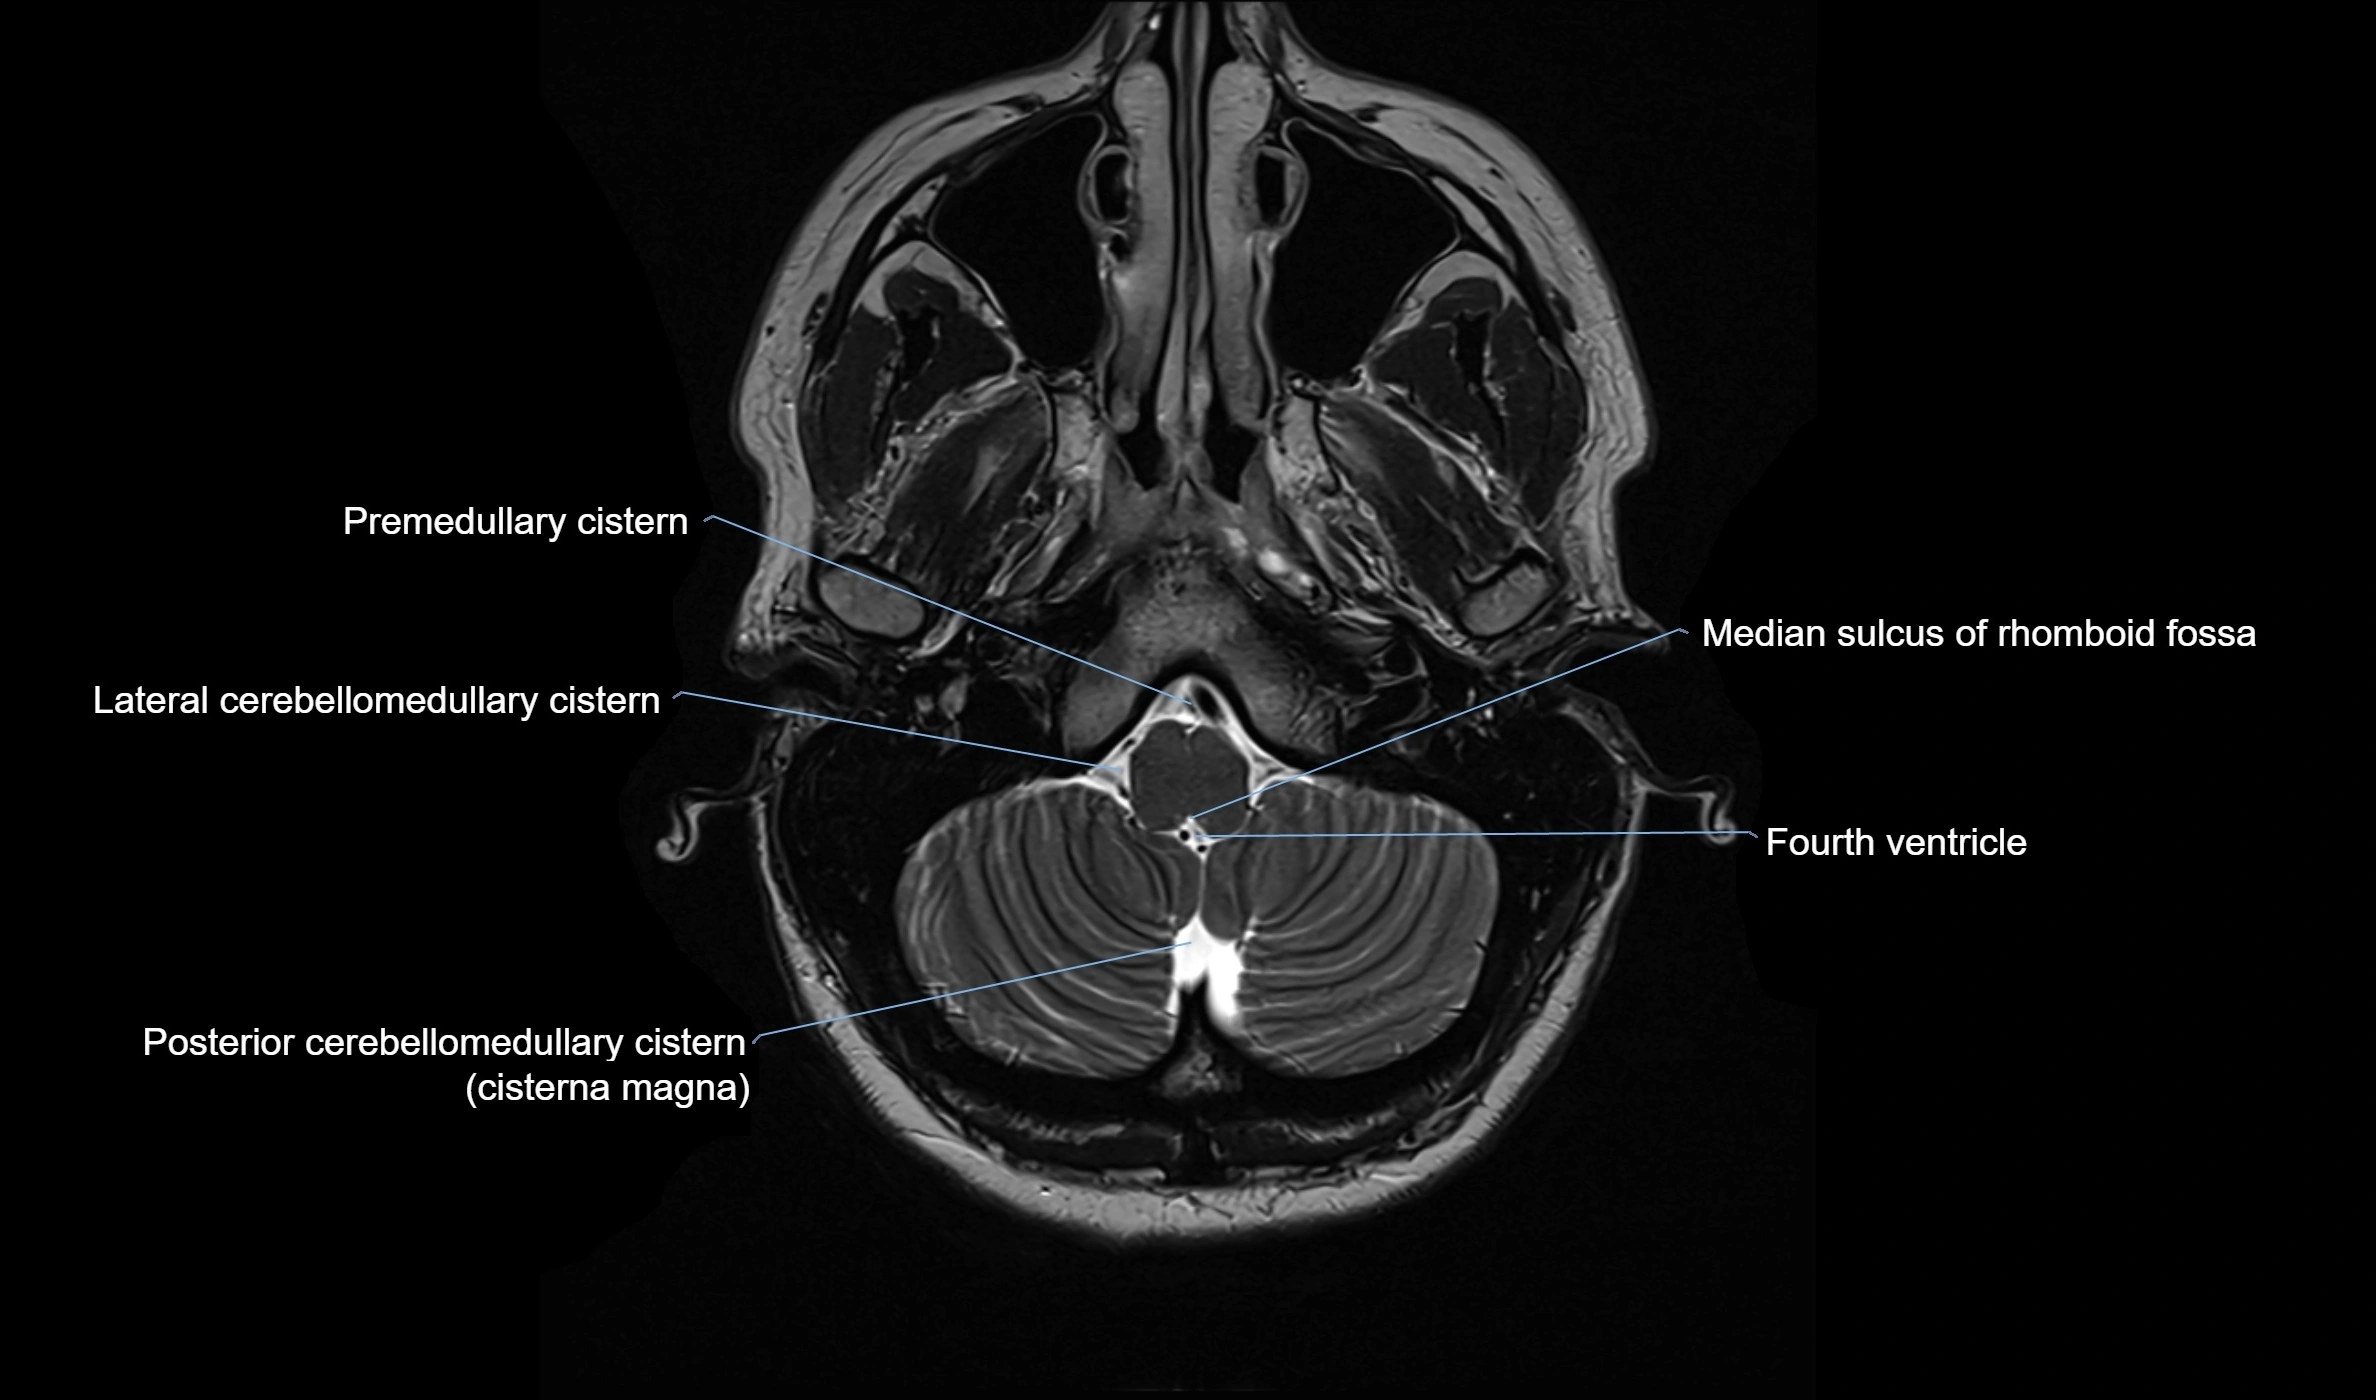

MRI images

image